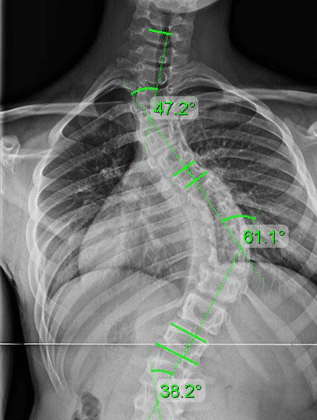

فعالية الحزام تعتمد على العمر ومرحلة النمو:

فعال جدًا

من 8 إلى 13 عامًا

الانحناء بين 20 و45 درجة

فعالية متوسطة

من 14 إلى 16 عامًا إذا كان النمو ما يزال مستمرًا

فعالية أقل

بعد اكتمال النمو

عندما تكون درجة الانحناء أعلى من 45 درجة